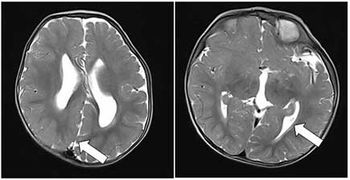

Case History: 15-month-old with focal seizure, developmental delay, disproportionate increase in size of head.